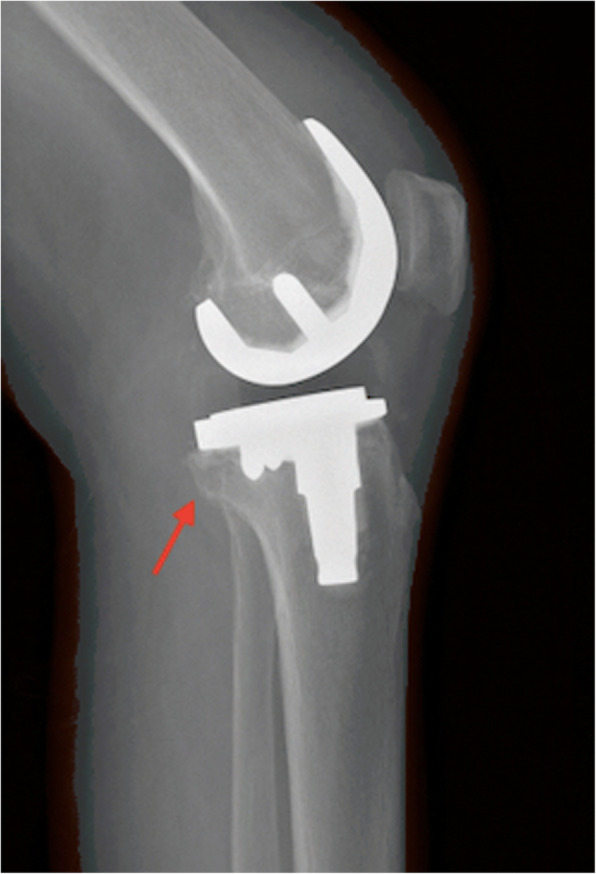

In the study group, complete reduction was achieved and maintained in all patients. Based on the radiographic evaluation, fracture healing occurred in all patients within 3 months (Fig. 4). No patient experienced knee instability. No patient walked with an assistive device, and no patient underwent a revision surgery.

Fig. 4.

Lateral X-ray showing bone healing after 3 months